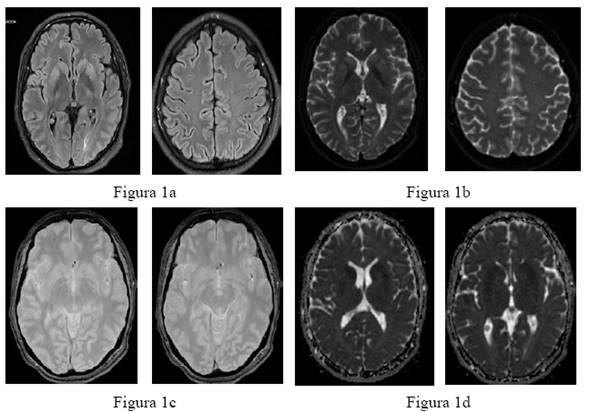

En julio del 2024 acude a clínica privada por cuadro clínico de dos meses de evolución caracterizado por síndrome vertiginoso, mioclonías, disartria, disminución de la agudeza visual, cuadro se exacerba con mioclonías generalizadas, mayor desorientación temporo espacial y cognitivo. Se realiza estudios complementarios de resonancia magnética nuclear de encéfalo con gadolinio mismo reporta hiperintensidad en T2 y flair de ganglios de base, en corteza frontal bilateral, además hiperintensidad parasagital probable proceso inmunomediado (Figura 1a-d).

Figura 1: Resonancia magnética nuclear de encéfalo con gadolinio. (FLAIR) A nivel subcortical temporo occipito parietal bilateral y periférico a los cuernos posteriores de los ventrículos laterales se observa muy tenue imagen isointensa (1a); imágenes ponderadas por difusión (DWI); hiperintensidad de ganglios de base bilateral (1b); Ax t2 FGRE: hiperintensidad lóbulo frontal (1c); ADC: imagen isointensa en T1 y T2 (1d). FLAIR: Fluid-Attenuated Inversion Recovery. DWI (Driving While Intoxicated).

En el caso presentado la enfermedad avanzó de manera acelerada, resultado similar al de otros estudios como el de Villagra-Sancho D. et al, estableciendo que la enfermedad progresa rápidamente, y la mayoría de los pacientes fallecen dentro del primer año de aparición de los síntomas un tiempo de supervivencia medio de ocho meses 6; de manera similar a otros estudios las Resonancia Magnética con secuencias de tiempo de repetición largo FLAIR (Fluid-Attenuated Inversion Recovery) y DWI (Driving While Intoxicated) fueron patológicas, y el patrón de afectación cortical difusa y de los ganglios basales fue el más frecuente 5,6.

La prueba definitiva mostró positivo para la proteína 14.3.3.UA/ml en el líquido cefalorraquídeo; resultado que guarda relación con otros que establecen que el 65 % de los casos positivos presentaron proteína 14.3.3UA/ml en el líquido cefalorraquídeo 6. Es importante considerar que, si bien el diagnóstico definitivo se basa en los hallazgos clínicos e histopatológicos, el uso de estudios complementarios también permite su diagnós tico con cierto grado de confianza; así por ejemplo el uso de RM en pacien tes que presentan síntomas compatibles con la enfermedad aumenta la sensibilidad del diagnós tico hasta el 98 %; los hallazgos característicos en esta consisten en hiperintensidad de la corteza cerebral y/o núcleos de la base, especialmente caudado y putamen; en este sentido hay estudios que señalan que la RM con secuencias de DWI constituye una prueba especialmente sensible para el diagnóstico de la enfermedad, aunque su sensibilidad disminuye en estadios precoces, como lo indican García-Ortega YE et al 7. La alta especificidad y la alta sensibilidad de la RT-QuIC, junto con un diagnóstico clínico y patrón radiológico característico, se plantean como alternativa al diagnóstico de certeza anatomopatológico 7,10.